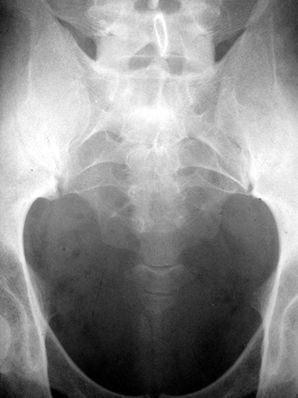

尾骨骨裂图片x光

尾骨骨裂图片x光,尾骨骨折x光图片

尾骨的x光片,烦请专业人士看看

请医生或者懂的人给看看照的x光片

看图论病(尾椎骨折)

其余的尾骨成小团块状,各